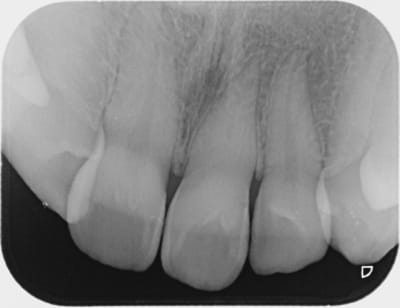

Cas simple et pourtant ... j'ai été obligé de prendre un risque . Lequel ?

C'est un blanchiment interne comme si l'endo était faite (après recherche effrénée d'un hypothétique canal), et après contrôle +++ d'une isolation +++ . La patiente n'a aucun souvenir d'un traumatisme sur cette dent .

Le protocole est le même que pour une dent dépulpée ; isolation en regard présumé du canal , un peu plus parce que j'ai cherché un moment en plusieurs séances . Perborate , et voilà .

Si on décide d'être le moins invasif , j'ai jugé raisonnable de tenter quand même malgré l'impossibilité de repérage de l'entrée du canal . Faire une facette c'est passer un cap , et je n'ai de prothésiste capable de reproduire les stries visibles sur la photo de départ de tout façon donc je n'ai compté que sur moi même .